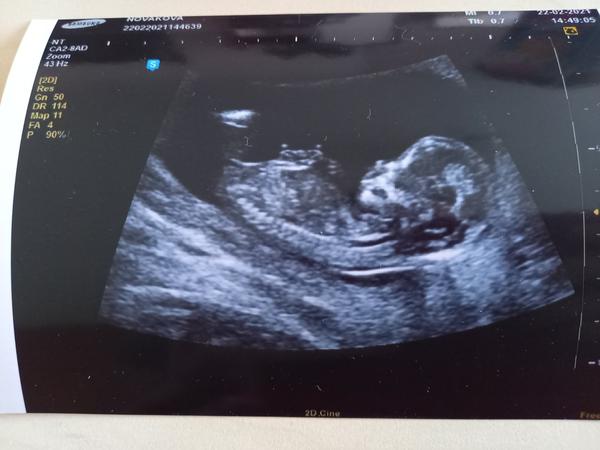

@misak48 ani nemluvte. Ultrazvuk vysel pekne, ale krev spatne, takze celkovy vysledek vysel na hrane a museli jsme do nemocnice na podrobnejsi ultrazvuk....naprosto nas to vystresovalo, tam to nastesti dopadlo dobre, melo by to byt v poradku 🙈 toto tehotenstvi si "uzivame" nejdrive potrat, pak na zacatku tehu covid, pak nejaka strevni bakterie a viroza, pak na ultrazvuku nebyl videt plod a ted zase screening 🙈 asi me odvezou.